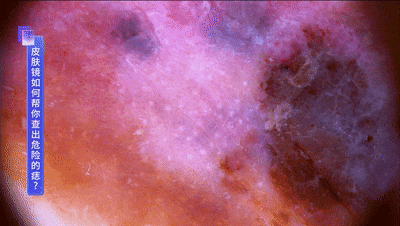

而且恶性黑色素瘤,会有不规则的蓝白结构,血管供应丰富等特点。↓